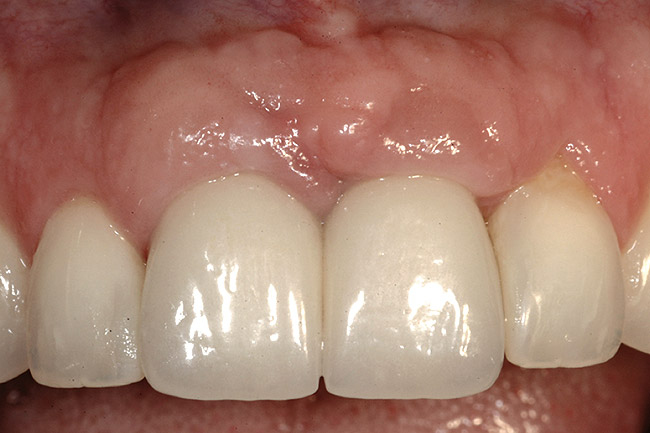

The most predictable of all presentations is patients who need multiple teeth removed and have no periodontal disease. The challenges in these patients are usually related to whether to use implants vs a fixed partial denture and, if implants are used, how many to use and where to place them. The answers generally depend on which teeth are being removed. For example, if the two maxillary centrals are being removed and have good bone, placing adjacent implants can result in a predictable and esthetic final result; because the papilla between the central implants and the adjacent laterals will be excellent, the facial gingival margins can be easily augmented, if necessary; and the papilla between the central implants should remain within 1 mm to 2 mm of the pre-extraction papilla level, as long as the implants are placed 3 mm apart and the interproximal crest of bone is maintained (Figure 5, Figure 6, Figure 7, Figure 8 and Figure 9). In this case the patient could be treated with a fixed prosthesis using the lateral incisors as abutments. However, because the interproximal bone between the extracted centrals most likely will be lost, the risk of greater recession of the papilla between the centrals exists. Soft-tissue augmentation also would be able to create an excellent papilla in this location before completing the restoration.

Figure 9  The final restorations exhibit a minimal 1-mm to 1.5-mm change in papilla height when compared with the pre-extraction height.

Figure 9